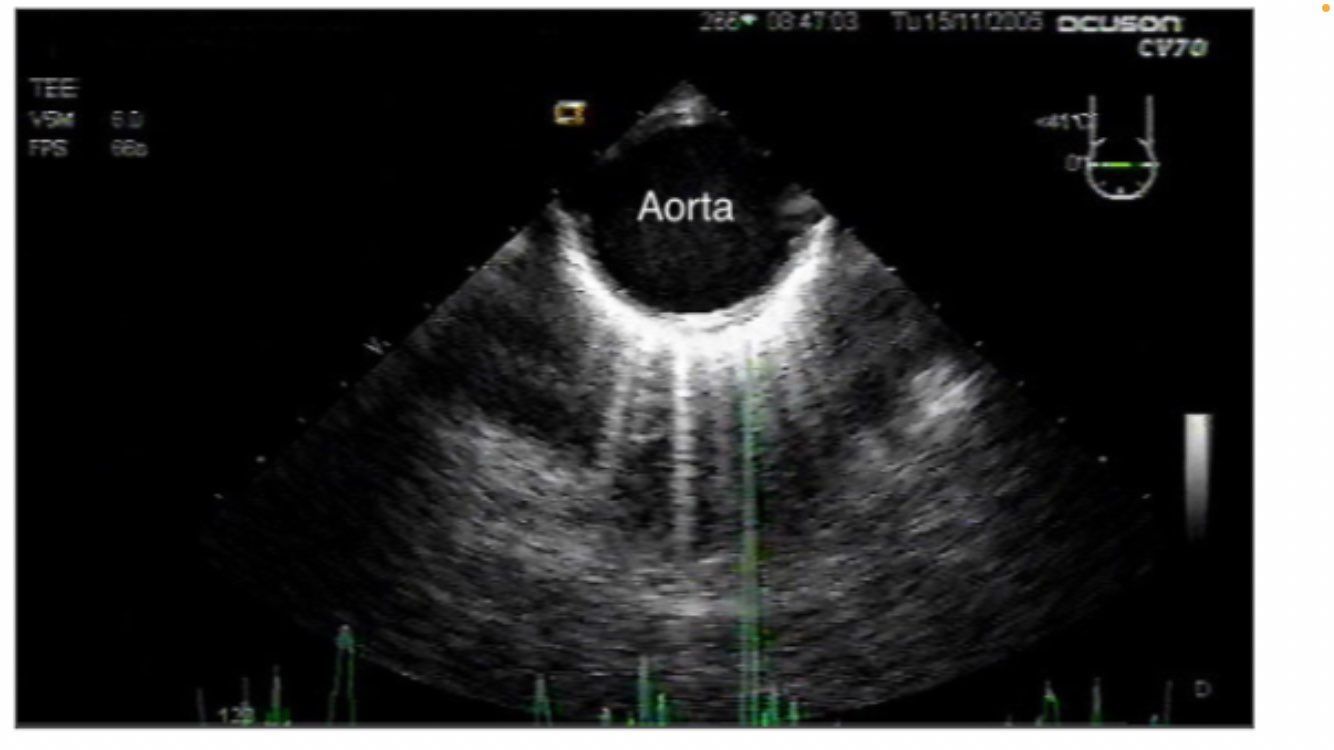

descending aortic SAX and LAX

descending aortic SAX

descending aortic short axis

aortic long axis

NO DISSECTION